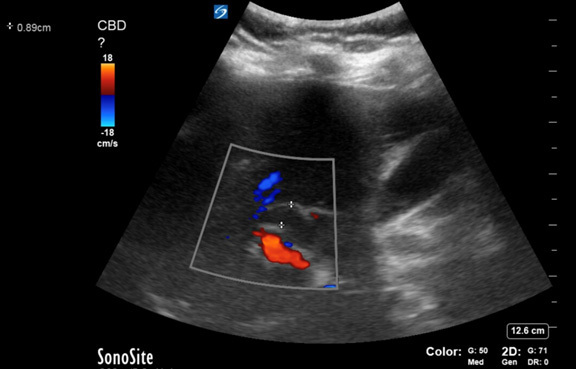

Figure 3. Cholangitis Resulting from Biliary Obstruction |

Evidence of dilated common bile duct measuring at 0.89 cm in a case of cholangitis resulting from biliary obstruction. Note the common bile duct is sitting above the hepatic artery. |

Image courtesy of Daniel Migliaccio, MD, FPD, FAAEM. |